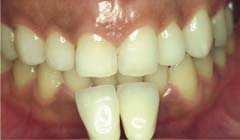

■ポーセレンベニア■

施術前

施術後